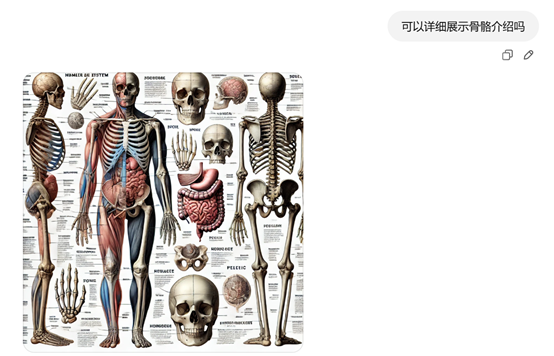

提示词:用一张图片介绍人体各个结构。

这个人体介绍图片就丰满很多,放在医疗介绍或PPT里应该不错吧。以后做各种宣传资料不愁找不到量身定制的图片了。

如果不满意,可以基于该图片继续发问,例如,我们想看上面人体介绍的骨骼。提示词:可以详细展示骨骼介绍吗?